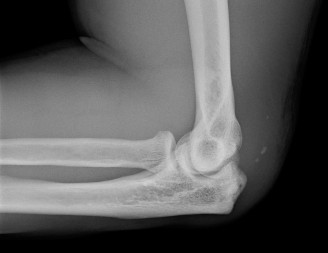

A 20-year-old male presents to the office with right elbow pain. He states he fell 5 years ago and was told h…

A 23-year-old, semi-professional football linebacker presents with left elbow pain after a game. He extended …